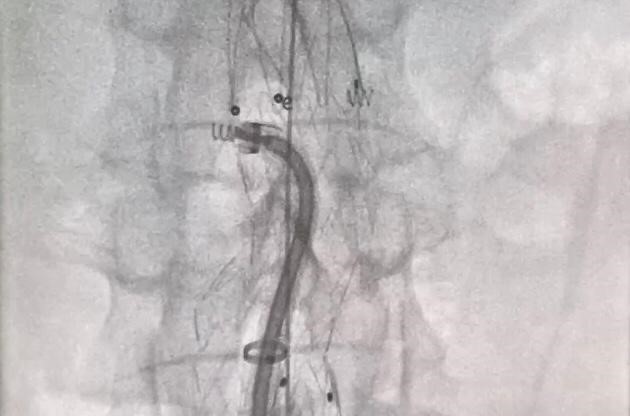

В рамках мероприятия М. А. Чернявский, совместно с заведующим отделением отделением рентгенохирургических методов диагностики и лечения НМИЦ им. В. А. Алмазова Д. Д. Зубаревым провели две показательные операции. Первому пациенту был имплантирован стент-графт в брюшной отдел аорты с последующим использованием системы фиксации Heli-FX™. Второму было выполнено эндопротезирование брюшного отдела аорты и почечных артерий по методике «Chimney». Обе операции проведены под местной анестезией через проколы на бедрах. Процедура имплантации стент-графта длилась около 50 минут. В настоящее время состояние обоих пациентов стабильное, течение послеоперационного периода без особенностей. В дальнейшем они продолжат наблюдаться у специалистов НМИЦ им. В. А. Алмазова. В завершении мероприятия участники поделились собственным опытом по применению системы Heli-FX™.

Процесс фиксации стент-графта